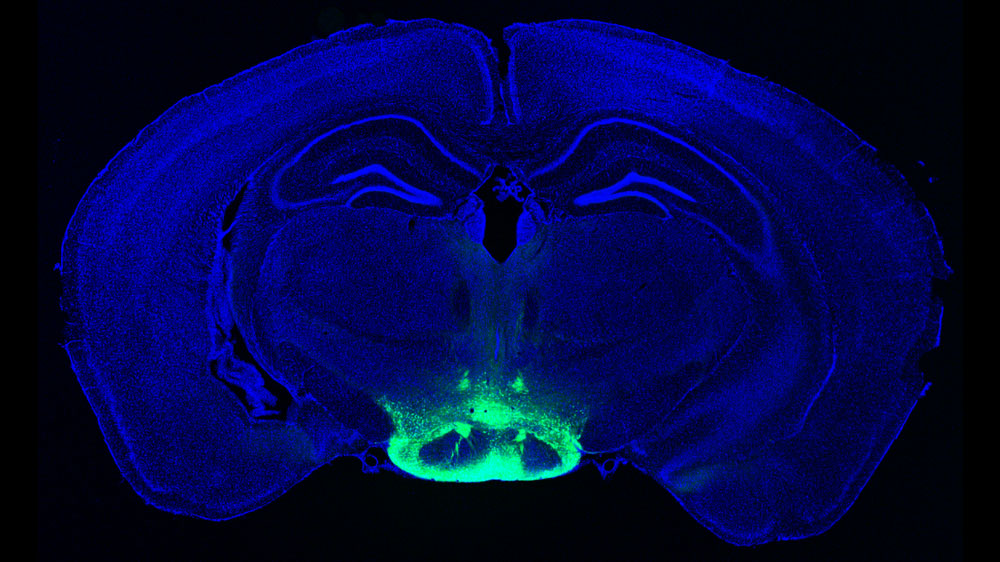

Scientists have identified neurons in the brain that may contribute to some of the earliest symptoms of Alzheimer’s disease. The cells occur within a region of the hypothalamus that could be a good target for potential new drugs to treat the disease.

Image: Courtesy of the researchers